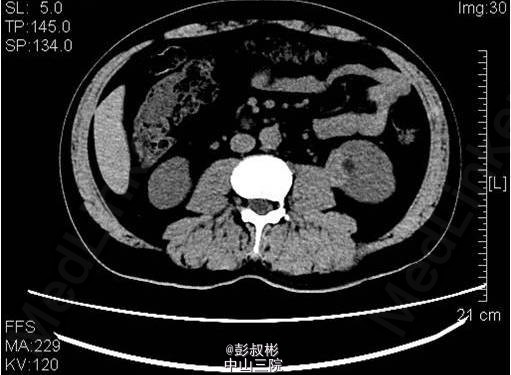

3、既往病史:高血压,高尿酸,高血脂6年,2013年行“右输尿管结石碎石取石术” 4、入院查体:未见明显异常体征。 5、影像学检查:中下腹部CT平扫+增强+CTU:左肾中盏可见结节状高密度影,直径约为6mm,基本同前。左肾下部可见大小约为36×21×23mm稍高密度影突出于包膜生长,较前明显增大,凸向肾外生长,浅分叶,其内见脂肪密度影,增强扫描可见轻度强化,病灶与左侧腰大肌关系密切。